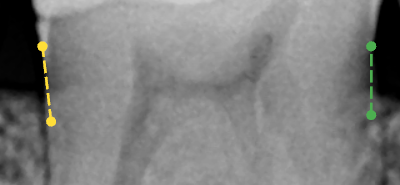

Results of the bone level (RBL) analysis - Dashed lines appear on the image where bone levels were measured. The color of a line (white, green, yellow, orange, or red) is determined by the severity of the calculated bone loss.

Note: You can position your pointer over a bone level measurement to view the calculated percentage of bone loss.